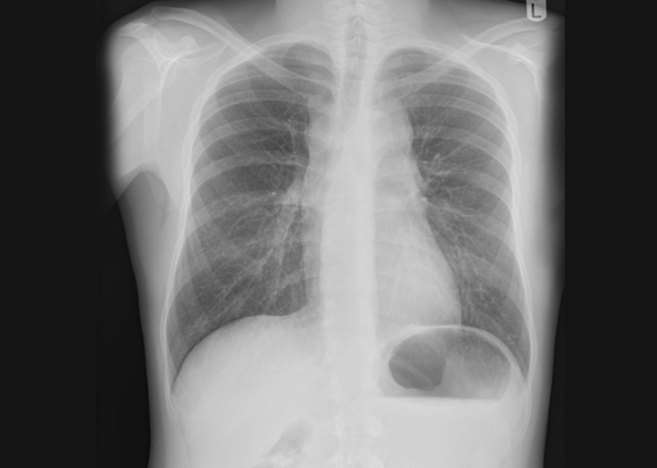

A male adult in his 20s presented to the North Tees and Hartlepool NHS Foundation Trust hospital with a history of persistent cough and underwent a chest radiograph (CXR) as requested by his GP. The acquiring radiographers did not identify any abnormalities during their PCE. The patient was sent home, consistent with existing protocols.

Harrison.ai CXR identified 3 critical findings, including hilar lymphadenopathy, superior mediastinal mass and inferior mediastinal mass.

The reporting radiographer immediately reviewed the flagged case and agreed with Harrison.ai CXR’s findings, scheduling the patient’s CT scan for the next day. The radiographic appearances indicated a range of potential diagnoses including lymphoma, a significant concern that necessitated urgent follow-up. This change in workflow meant that instead of waiting for reporting in a chronological order (which could take up to a few days depending on staffing levels and CXR volumes), the patient’s images were reported almost immediately. This rapid response helped to ensure timely diagnosis and intervention, potentially saving days on the patient’s pathway.